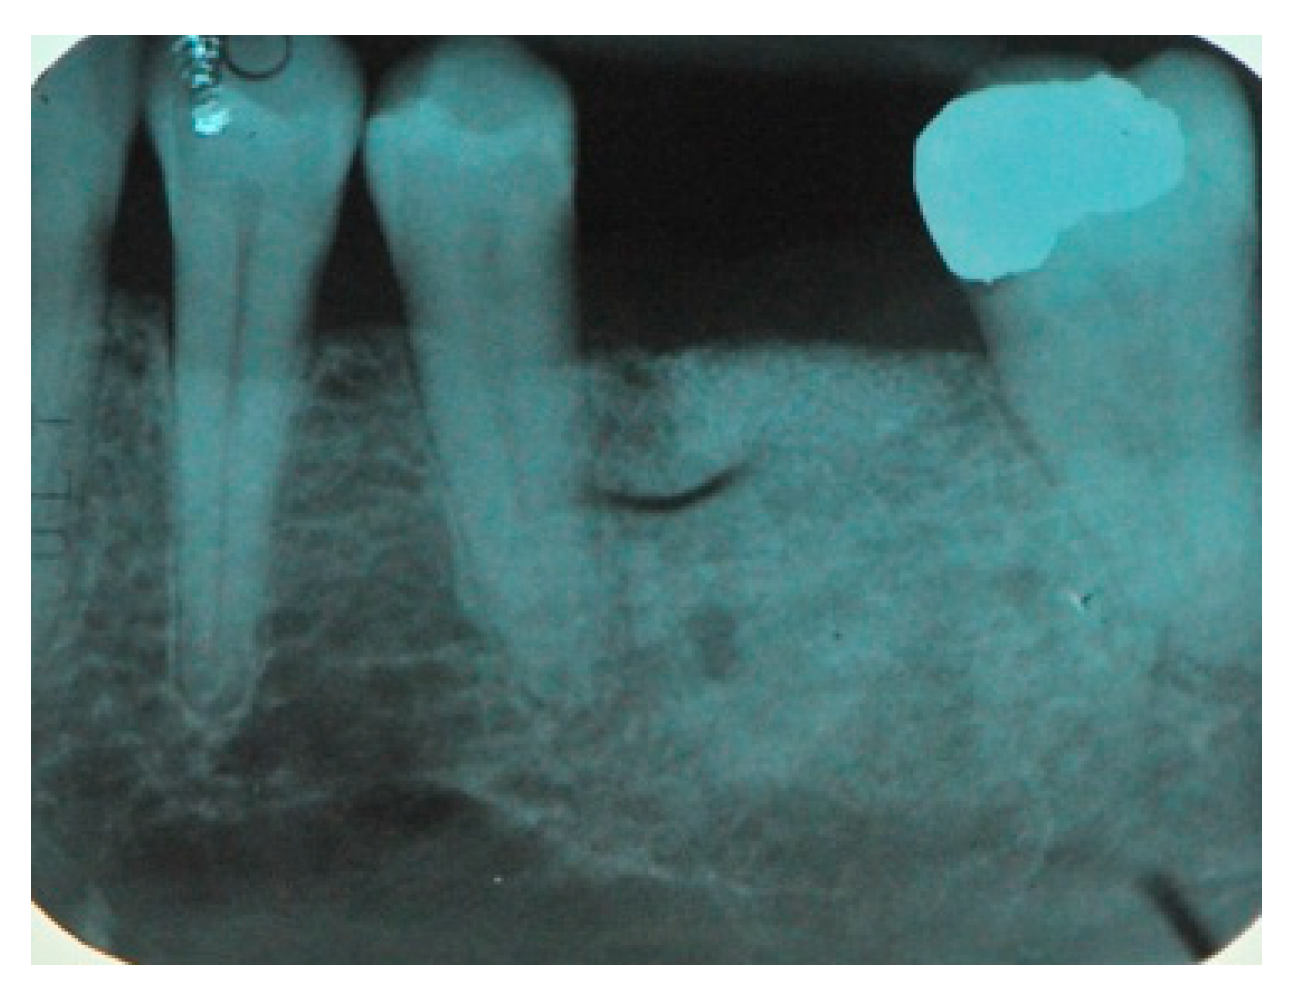

- The presence, clinically and radiographically (intraoral radiographs, panoramic, CT scans) assessed, of horizontal, vertical or mixed bone defects of the maxillary bones in particular the presence of residual bone <8 mm in height and <5 mm in width.

- Flap design: Soft tissue management should be as accurate as possible. The design of the flap should ensure a tension-free primary closure of the wound even after voluminous grafting of the defect. One option (preferred especially in wide vertical defects) is the execution of the so-called “poncho” flap. This technique includes a high vestibular incision of the mucosa, muscle and periosteum in order to undermine the preparation of the flap and to achieve its mobilization, followed by a deep incision in the buccal area with two additional vertical incisions that are performed at an appropriate distance from the occlusal area and the site of augmentation. After the incision, the preparation of a muco-periosteal flap and the remotion of scar tissue, a full thickness flap is raised until the bone defect is uncovered [17,18,19,20]. Finally, the positioning of the customized titanium mesh is passively tested to evaluate its fit intra-operatively (Figure 2, Figure 3, Figure 4 and Figure 5).